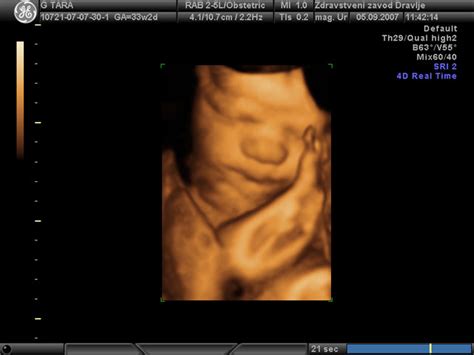

Prvi otrokovi gibi v maternici so pogosto opisani kot nežno migetanje ali "metuljčki v trebuhu". Te občutke običajno začnejo mamice zaznavati med 16. in 22. tednom nosečnosti. Tiste, ki so noseče prvič, lahko te nežne gibe sprva zamenjajo za prebavne procese ali druge telesne občutke. Ženske, ki so že bile noseče, te gibe pogosto zaznajo prej, saj že poznajo ta specifičen občutek. Znanstvene raziskave kažejo, da se lahko otrokovo premikanje zazna že med 16. in 24. tednom nosečnosti. Občutki se lahko razlikujejo - od udarcev, migetanja do žgečkanja, odvisno od stopnje nosečnosti in položaja otroka.

Tako imenovano "zgodnje brcanje" morda ne bo zelo pogosto. V začetni fazi nosečnosti lahko v trebuhu začutite nekaj zgodaj zjutraj, nato pa znova šele naslednji dan. Ko nosečnost napreduje, otrokovo gibanje postaja bolj izrazito. V zadnjem trimesečju nosečnosti boste otrokovo gibanje zaznavale zelo pogosto, lahko boste celo predvidele, kdaj bo otrok najbolj aktiven. Zanimivo je, da je otrok pogosto najbolj aktiven takrat, ko se mati poskuša umiriti in zaspati.

Znanstvene raziskave in izkušnje porodničarjev ponujajo več razlag za ta pojav. Otrokov položaj v maternici igra ključno vlogo. Najpogosteje se otroci obrnejo z glavico navzdol, pri čemer je hrbet lahko obrnjen proti levi ali desni strani. Če je hrbet obrnjen proti levi, lahko otrok z nogicami brca pod desnim rebrnim lokom, torej na desni polovici trebuščka. Nasprotno, če so nogice obrnjene navzdol, bodo gibi bolj občuteni v spodnjem delu trebuha.

Pomembno je razumeti, da je maternica zgrajena tako, da nudi otroku prostor za rast in gibanje. V zgodnejših fazah nosečnosti, ko je maternica manjša, so gibi bolj enakomerno porazdeljeni. Ko pa otrok raste, se lahko njegovi gibi koncentrirajo na določena območja. Če ima otrok nogice obrnjene navzdol, bodo gibi, ki jih povzročajo te nogice, naravno bolj občuteni v spodnjem delu trebuha.